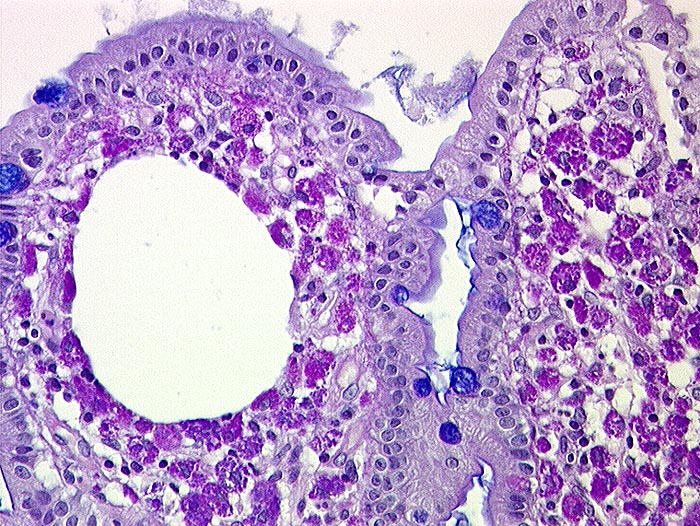

PathoPic ID 434 - Morbus Whipple

Morbus Whipple

Entzündung infektiös

Dünndarm

Darm, Anus

Ektatisches Lymphgefäss in der Dünndarmzotten und massenhaft PAS positive Makrophagen im Stroma.

Elektronenmikroskopisch Stäbchenbakterien in den Makrophagen. Ziehl Neelsen negativ.

Histologie